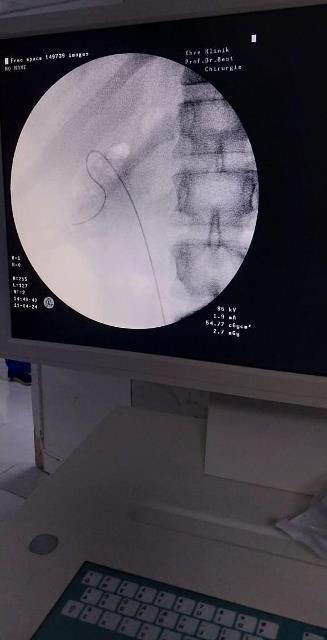

نجاح أول عملية لجراحة المسالك البولية بمستشفى مدينة الشروق.. صور

أشادت الدكتورة أمل إسماعيل، مدير عام المستشفى المركزى فى مدينة الشروق، بفريق المسالك البولية الخاص داخل المستشفى، بعد نجاحه فى إجراء أول عملية جراحية من نوعها داخل المستشفى، لإزالة حصوة بالحالب الأيمن لسيدة.

أوضحت مدير عام المستشفى المركزى فى مدينة الشروق، أن هذه العملية تأتى فى إطار استحداث تخصصات جديدة بمستشفى الشروق المركزى، طبقاً لتوجيهات محمد شوقى مدير مديرية الشئون الصحية بالقاهرة، والدكتور طارق إدريس مدير الشئون العلاجية بمديرية القاهرة؛ لإضافة الخدمات التى يحتاجها المريض والتى كان يضطر إلى العلاج خارج مدينة الشروق، لعدم وجود الإمكانيات.

أضافت الدكتورة أمل إسماعيل، أن المريضة حضرت للمستشفى فى حالة أعياء شديد، تعانى من جود حصوة بالحالب الأيمن، مع وجود ضيق شديد فى الحالب، مما أدى إلى إرتجاع البول الحالب والكلى اليمنى.. مشيرةً أنه تم على الفور تجهيز المريضة لدخول غرفة العمليات، والتى أجراها كلاً من: "دكتور محمد سيد اخصائى جراحة المسالك البولية، الدكتور أحمد عبدالله أخصائى التخدير، دكتور اسلام حمدى إشراف فنى، دكتور أحمد جمال إشراف إدارى، عمرو موسى ، فادى إسحاق من فريق التمريض"، والحصوة تم تفتيتها بجهاز التفتيت مع تركيب دعامة بالحالب الأيمن بمنظار المسالك البولية "Uretroscopic Double J Stent Insertion".

وأكدت الدكتورة أمل إسماعيل ، أن نجاح العملية يُعد نقلة علمية ومواكبة حقيقية للأساليب العلمية الحديثة، فى مجال جراحة المسالك البولية، خاصة أن العملية هى الأولى من نوعها فى مستشفي الشروق المركزي .